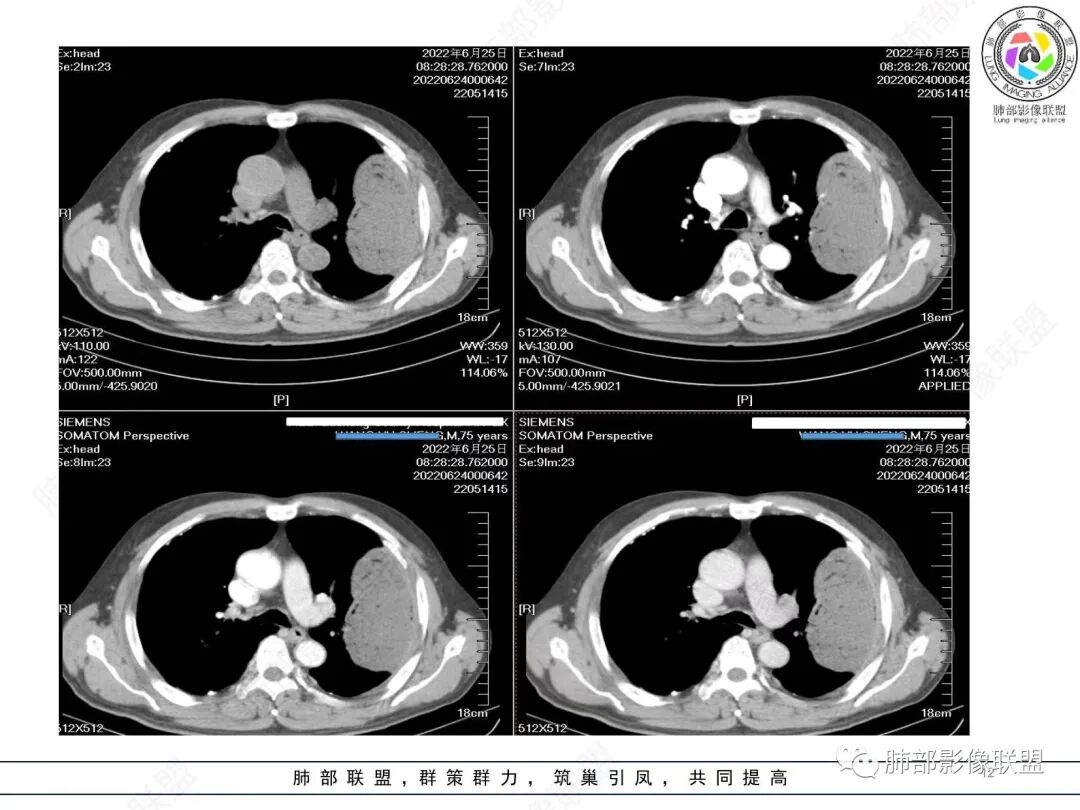

左肺上叶大肿块,膨胀性生长,边界清,密度较低,见部分坏死区,强化弱,肿块见支气管充气V扩张征,分布僵直,枯树枝特点,另一个重要特点血管造影征,淋巴瘤,肿块长轴与胸膜平行,与隐球菌鉴别,隐球荚膜抗原检查,明确诊断经皮肺穿刺。另胸膜钙化(问诊既往有无患胸膜炎病史)。

老年男性,糖尿病病史,消瘦、乏力三个月,影像表现左肺上叶胸膜下团块,有一定张力,内部疏松,可见支气管影及坏死区,增强病灶边缘环形强化,内部未见强化,考虑炎性肉芽肿病变,隐球?奴卡?放线菌?鉴别淋巴瘤。

左肺上叶胸膜下肿块,宽基底与胸膜相连,跨叶裂,边缘清晰膨隆,其内支气管充气,部分扩张、僵直,无明显强化,血管造影征,考虑淋巴瘤,鉴别腺癌

左肺胸膜下巨大占位,跨叶裂,宽基底与胸膜相连,胸膜钙化,平扫密度较低,强化不明显,可见内部血管显影,支气管充气征和扩张,考虑为恶性,倾向于淋巴瘤

左肺上叶肿块,宽基底与胸膜相连,跨叶裂,边缘清晰膨隆,可见小分叶,其内支气管充气,部分扩张、僵直,呈枯枝征,支气管达边征,增强无明显强化,可见血管造影征,考虑恶性病变,淋巴瘤,鉴别粘液腺癌。

我要修正一下观点了:仔细看了视频,肿块占位效应明显,对周围血管,支气管有推挤,增强后强化不明显,NSE增高,半年体重下降25公斤,虽然有内部支气管扩张,血管漂浮,边界清楚支持淋巴瘤,但强化太低,膨隆,占位推挤太明显(淋巴瘤一般没有这么明显的占位效应),胸膜关系有载桩,恶病质明显(乏力,半年体重下降了25公斤),NSE也明显增高,就不支持淋巴瘤了。还是考虑外朝内的恶性肿瘤,间质来源的肉瘤伴有神经内分泌分化或者大神泌。

不支持淋巴瘤的有四点:1、对周围血管支气管推挤明显。2、胸膜有栽桩,3、强化太弱(淋巴瘤一般还是中度以上甚至高度强化多见),4、NSE升高明显,体重下降太明显。

1)部位:周围型或中央型软组织肿块,以周围型为多见,且肿瘤多位于肺上叶。如本例:该肿瘤位于左肺上叶。

2)大小及形态:由于本病恶性程度高,早期症状不明显,发现时肿块均较大。如本例病变巨大。

3)肿块边界和边缘:多较清楚,呈圆形、类圆形,且由于肿块生长速度不均匀,可见分叶,毛刺少见。有报道肿块周围毛玻璃影是多形性癌特征表现。

4)密度:肿块平扫为软组织密度,由于体积较大,内部常见大片状坏死,可出现不规则厚壁空洞或坏死内多发无壁小空洞,坏死多不均匀:坏死灶内可见如柳絮样的斑片样强化灶,坏死边缘与非坏死区分界不清本例坏死较明显,密度不均匀。

5)肿瘤强化方式:肺部恶性肿瘤强化程度与其血供丰富程度相关,血供丰富多强化明显,反之则较差。由于PSC 周边实性部分富血供及内部黏液变性、坏死,增强后肿块多数呈轻-中度边缘环形强化或不均匀小斑片状强化。国外学者对照病理发现肿瘤细胞或胶原组织增强扫描时强化,无强化的低密度区代表了黏液样变性区和出血坏死区。